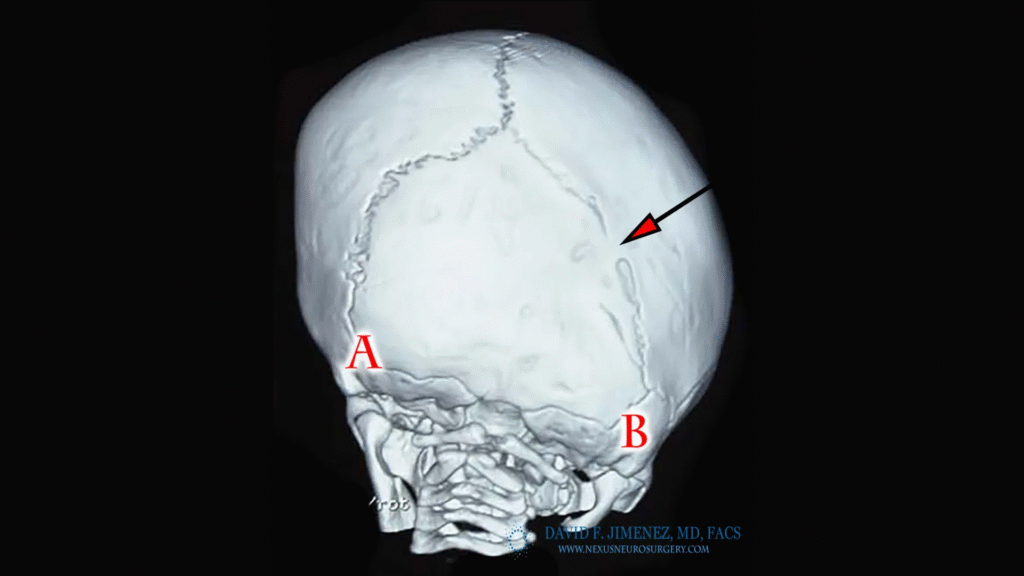

At El Paso Craniofacial Team, the primary treatment for craniosynostosis is surgery. First performed in the late 1800s, surgical approaches have continued to evolve and improve. The two main approaches are Calvarial Vault Remodel (CVR) and endoscopic-assisted surgery, with each tailored to the child’s age, the affected suture, and the severity of the condition.